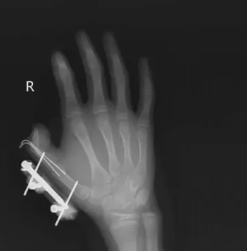

前段时间,湖南的一名 14 岁的小孩在爸爸网购冰激凌的箱子里发现了用于冷藏的干冰,以为是玩具,便捏在手里反复摇晃。结果密封袋里的干冰突然爆炸,小朋友的右手瞬间鲜血直流,拇指虎口处被撕开一道约 10 厘米的伤口,拇指骨折。